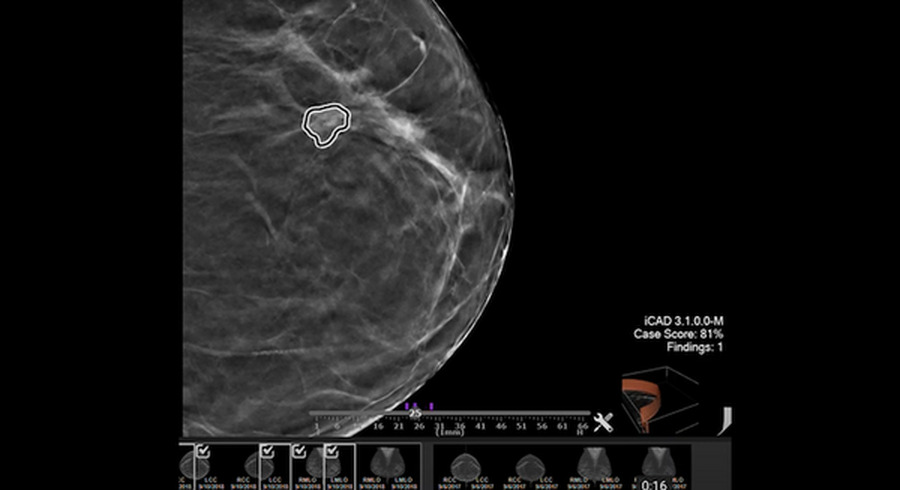

放射線技師はマンモグラムの読影を支援するiCADの革新的なProFound AIソフトウェアを使用している。このようなAIソリューションにより、がんの早期発見、乳房密度のカテゴライズ、女性ひとりひとりのスクリーニングマンモグラムに基づいた短期的な個別乳がんリスクの正確な評価が可能になる。VMware vSphereを使用して高度なワークロードを実行することは、データ集約型アプリケーションを病院のインフラストラクチャに簡単に統合できるため、iCADを利用するヘルスケア現場の顧客にとって重要。